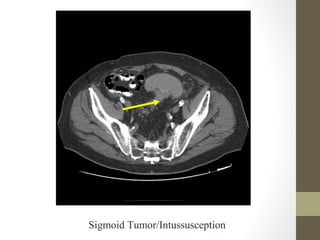

Radiology- CT Scan

diverticulitis, abscess, mesenteric ischemia, masses, obstruction

Sigmoid Tumor/Intussusception

Radiology- CT Scan •Detect leaking AAA (in stable patient) • Evaluate for renal calculi, appendicitis, perforation (free air), diverticulitis, abscess, mesenteric ischemia, masses, obstruction • Sensitivity and specificity vary • Not a place for unstable patients • Contrast • PO and IV contrast in most patients • sometimes rectal contrast is helpful to look for large bowel problems (appendicitis) • In patients with renal insufficiency • give IV contrast judiciously in patients • consider ultrasound as an alternative if possible • a creatinine > 1.5 usually requires bicarbonate and fluid hydration to minimize contrast nephropathy